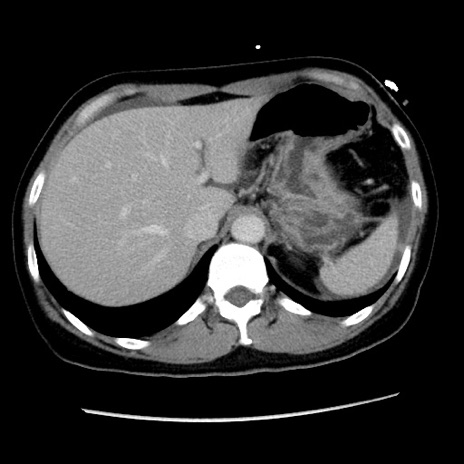

矢状断像

【症例】 50歳代女性

【主訴】 腹痛

【現病歴】前日生レバーを食べた。今朝に排便あり。 昼前に突然発症の腹痛を生じ、当院救急外来を受診した。

【身体所見】 意識清明、腹部:平坦、軟、下腹部やや左を中心に圧痛・反跳痛あり、筋性防御あり